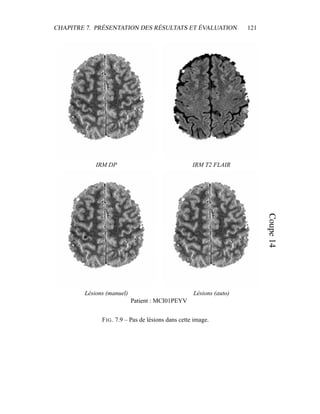

ment l’impasse sur certains processus décrits dans la littérature pour améliorer la

qualité visuelle de la segmentation – les contraintes sur le voisinage, par exemple

– puisque notre but est d’obtenir un critère sur l’intensité qui sera raffiné ensuite